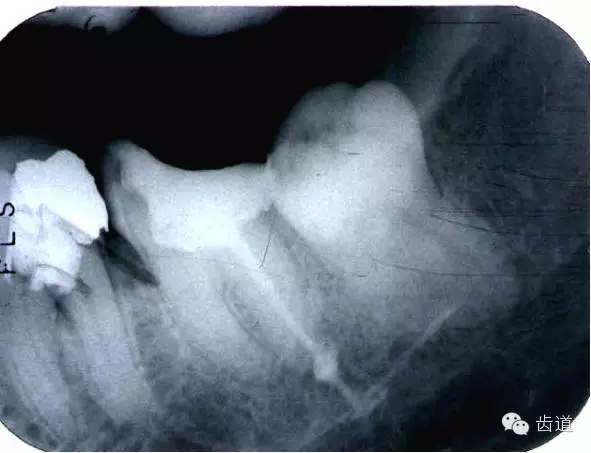

磨牙髓室頂、底距離接近時(shí),易將髓底穿孔。

左下6底穿

左上6底穿

根管壁穿孔多在根管彎曲處。

(3)髓室底穿孔:處理方法同上。同時(shí)找到根管口,按常規(guī)進(jìn)行根管預(yù)備和充填。如穿孔范圍太大易導(dǎo)致根分歧病變,予后欠佳。可行根管外科。

(4)根管壁形成臺(tái)階:先換小號(hào)銼去除臺(tái)階,再順序擴(kuò)挫。如根管壁穿孔,找到主根管進(jìn)行預(yù)備后,主根管及側(cè)穿道同時(shí)充填。在根尖1/3或根尖彎曲處側(cè)穿,根充后,配合根尖手術(shù)——根切+倒充填。